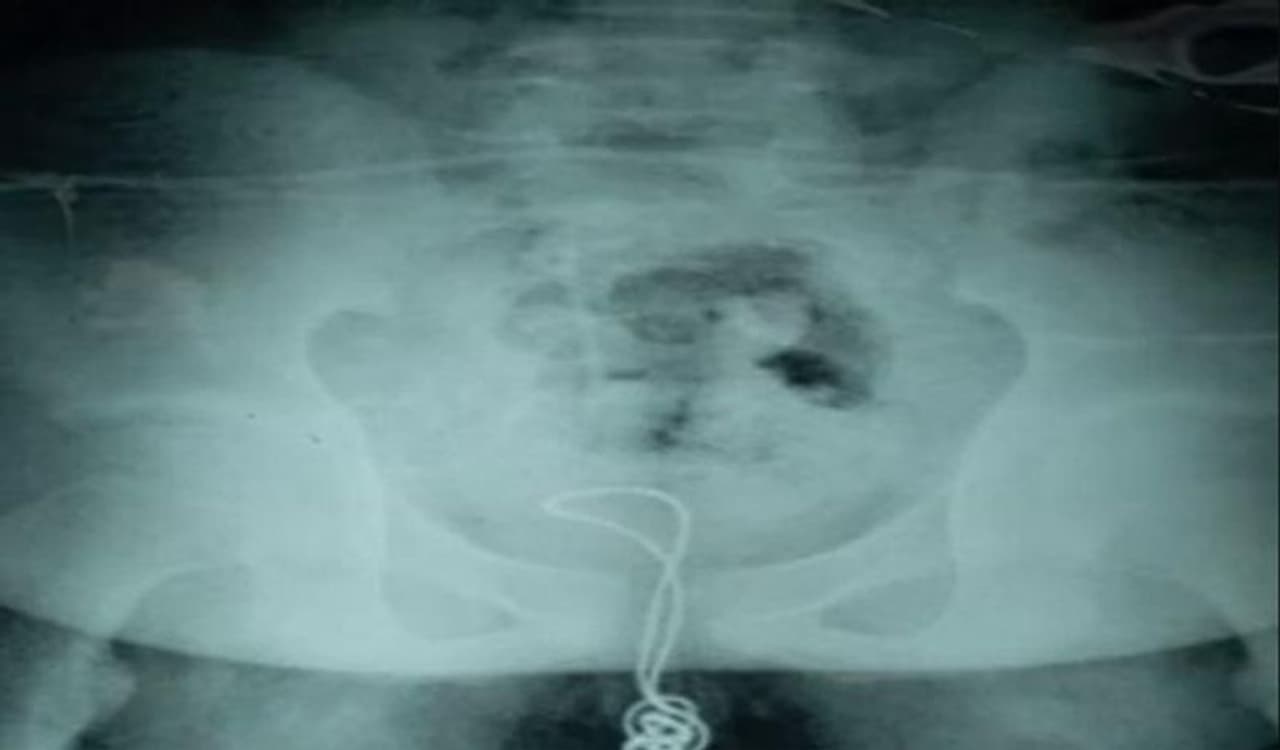

जब बच्चे की एक्सरे रिपोर्ट आई, तो सब हैरान रह गए। उन्होंने देखा कि बच्चे के ब्लेडर में दो फुट लंबी तार है। इसके तुरंत बाद बच्चे को एडमिट कर लिया गया।

डॉक्टर्स ने सर्जरी कर बच्चे के मूत्राशय से दो फुट की तार बाहर निकाली। जब बच्चे से इसके बारे में पूछा गया तो उसने बताया कि तीन महीने पहले उसने इस तार को प्राइवेट पार्ट के जरिये बॉडी में घुसाया था।

डॉक्टर्स ने सर्जरी के बाद बच्चे की जान बचा ली। उन्होंने कहा कि गनीमत है कि तार से बच्चे को कोई नुकसान नहीं पहुंचा। इस सर्जरी में घंटे का समय लगा। जिसके बाद 70 सेंटीमीटर लंबा तार बाहर निकाला गया।